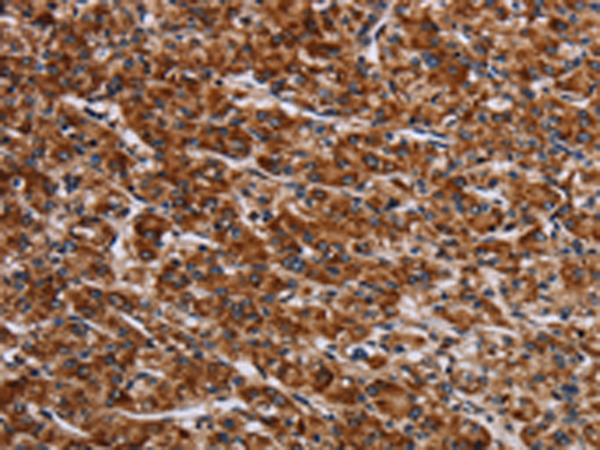

分类: 科研抗体货号: P08485别名: LIB应用: IHC反应种属: Human, Mouse, Rat